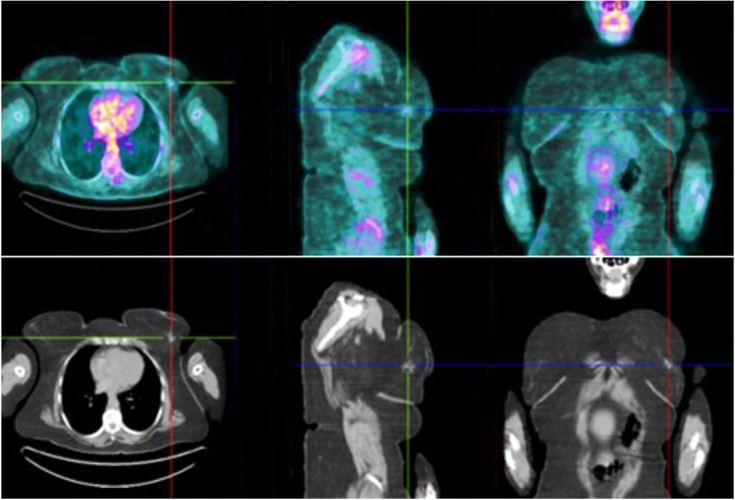

Intestinal lipomatosis is rare and often asymptomatic but can present with intestinal obstruction. Occasionally, metastatic breast cancer is identified in the ovary before a breast primary is discovered. We report the case of a 50-year-old woman diagnosed with synchronous intestinal obstruction due to lipomatosis, and incidental ovarian metastases from breast cancer. The patient presented with a 12-day history of nausea, diffuse abdominal pain, and constipation. An abdominal x-ray showed air-fluid levels, and computed tomography documented small bowel distention. An explorative laparotomy was performed, which revealed small bowel distention, an obstructive lesion of the ileocecal valve, three terminal ileum lesions, ascites, and heterogeneous ovaries. Right ileocolic resection and left oophorectomy were performed. The pathological diagnosis revealed lipomatous submucosal lesion of the ileocecal valve and ileum, and 17 lymph nodes, which were all negative for malignant cells. The oophorectomy revealed ovarian metastasis from breast carcinoma. Ascitic fluid was positive for malignant cells. Mammography and breast/axillary ultrasonography showed a solid nodule of the left breast, ductal carcinoma, and multiple enlarged left axillary lymph nodes, which were positive for neoplastic cells. Immunohistochemical evaluation showed hormonal receptor positivity and C-erb2 negativity. Breast magnetic resonance imaging showed a 14 mm left nodule and a positron emission tomography scan revealed F-FDG uptake in the left breast, left axillary lymph nodes, right ovary, and peritoneum. The tumor was staged as stage IV ductal breast carcinoma, cT1N1M1, Grade 2, Luminal B-like. The multidisciplinary oncological meeting proposed chemotherapy, and a re-staging breast MRI after chemotherapy, which showed a complete response. The patient started treatment with letrozole and remains disease-free 22 months after finishing chemotherapy.

肠脂肪过多症罕见且通常无症状,但可表现为肠梗阻。偶尔,在发现原发性乳腺癌之前,会在卵巢中发现转移性乳腺癌。我们报告一例50岁女性病例,该患者被诊断为因脂肪过多症导致的同步性肠梗阻,以及偶然发现的乳腺癌卵巢转移。患者有12天的恶心、弥漫性腹痛和便秘病史。腹部X光显示气液平面,计算机断层扫描记录了小肠扩张。进行了剖腹探查术,发现小肠扩张、回盲瓣梗阻性病变、三处回肠末端病变、腹水和双侧卵巢不均质。实施了右半结肠切除术和左侧卵巢切除术。病理诊断显示回盲瓣和回肠的脂肪性黏膜下病变,以及17个淋巴结,所有淋巴结均未发现恶性细胞。卵巢切除术显示为乳腺癌卵巢转移。腹水检查发现恶性细胞阳性。乳房X光摄影和乳腺/腋窝超声检查显示左乳实性结节、导管癌以及多个左侧腋窝淋巴结肿大,淋巴结肿瘤细胞阳性。免疫组化评估显示激素受体阳性,C-erb2阴性。乳腺磁共振成像显示左乳有一个14毫米的结节,正电子发射断层扫描显示左乳、左腋窝淋巴结、右卵巢和腹膜有F-FDG摄取。肿瘤分期为IV期导管性乳腺癌,cT1N1M1,2级,Luminal B样。多学科肿瘤学会议建议进行化疗,并在化疗后重新进行乳腺MRI分期,结果显示完全缓解。患者开始使用来曲唑治疗,化疗结束22个月后仍无疾病进展。